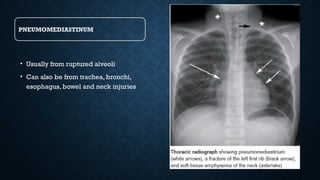

PNEUMOMEDIASTINUM

• Usually from ruptured alveoli

• Can also be from trachea, bronchi,

esophagus, bowel and neck injuries

CHEST XRAY FOLLOWING TRAUMA SHOWING AIR OUTLINING

MEDIASTINAL STRUCTURES AND SUBCUTANEOUS EMPHYSEMA

PNEUMOMEDIASTINUM • Usually fromruptured alveoli • Can also be from trachea, bronchi, esophagus, bowel and neck injuries

CHEST XRAY FOLLOWINGTRAUMA SHOWING AIR OUTLINING MEDIASTINAL STRUCTURES AND SUBCUTANEOUS EMPHYSEMA